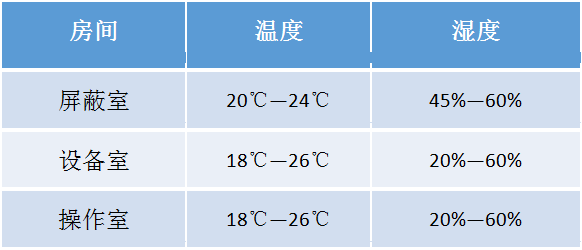

扫描架

Gantry

1.5T零液氦消耗(Zero Boil-off Magnet) 超导磁体

具有世界最高磁场均匀度水平的 1.5T 磁体,均匀度达到0.5ppm@50cmDSV 。且采用康达洲际独特的磁场校正技术HOSS(High Order Shim System),在患者进入磁体时,实现前所未有的磁场均匀度。 超高精度的 MRS、3.0T 水平的血管成像、大视野下的压脂技术(H-sinc)足以证明该磁体的超高性能。 而且,该磁体采用零液氦消耗技术(Zero Boil-off Magnet),能最大限度地减少因补充液氦而造成的停机时间,实现最大运营效率。 另外,检查仓内具有 LED 照明及送风功能,有效的减少患者幽闭恐惧。

主动屏蔽梯度线圈

Actively Shielded Gradient Coil

梯度切换率130T/m/s 最大梯度强度 33mT/m

检查床

Patient Table

Apsaras 采用了康达洲际独特的两层床板设计,该检查床在床长为 235cm 情况下实现了Z轴 280cm 的窜梭移动范围,并且没有增加安装面积;轻松实现全身类PET 、全脊柱、双下肢血管等大范围扫描技术。 另外,康达洲际检查床上下、前后移动都采用电动,检查床的高度可以下降至 45cm,便于行动不便的患者上下。